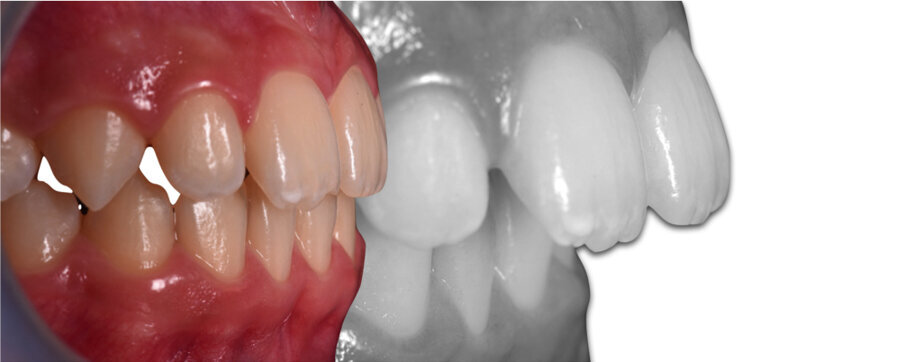

Forme di arcata (Fig. 1)

Forma C arcata larga e tondeggiante, palato basso Brachifacciale

Forma S Forma di arcata ovale ed armonica Mesocefalo

Forma 0S Forma di arcata squadrata Mesocefalo

Forma F Forma di arcata triangolare